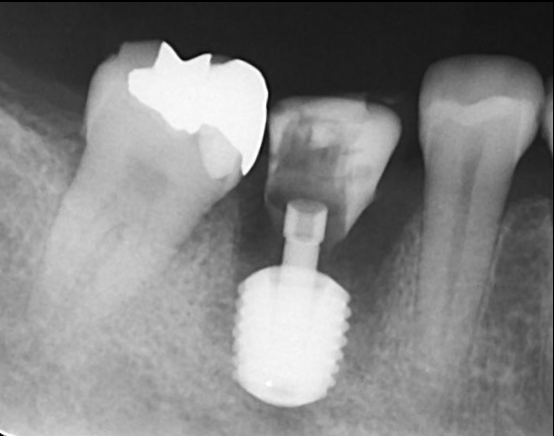

インプラント埋入後

仮歯SET後のデンタルX線写真

仮歯の状態で8週間過ごしてもらいます。その後型取りを行いセラミックをSETしていきます。